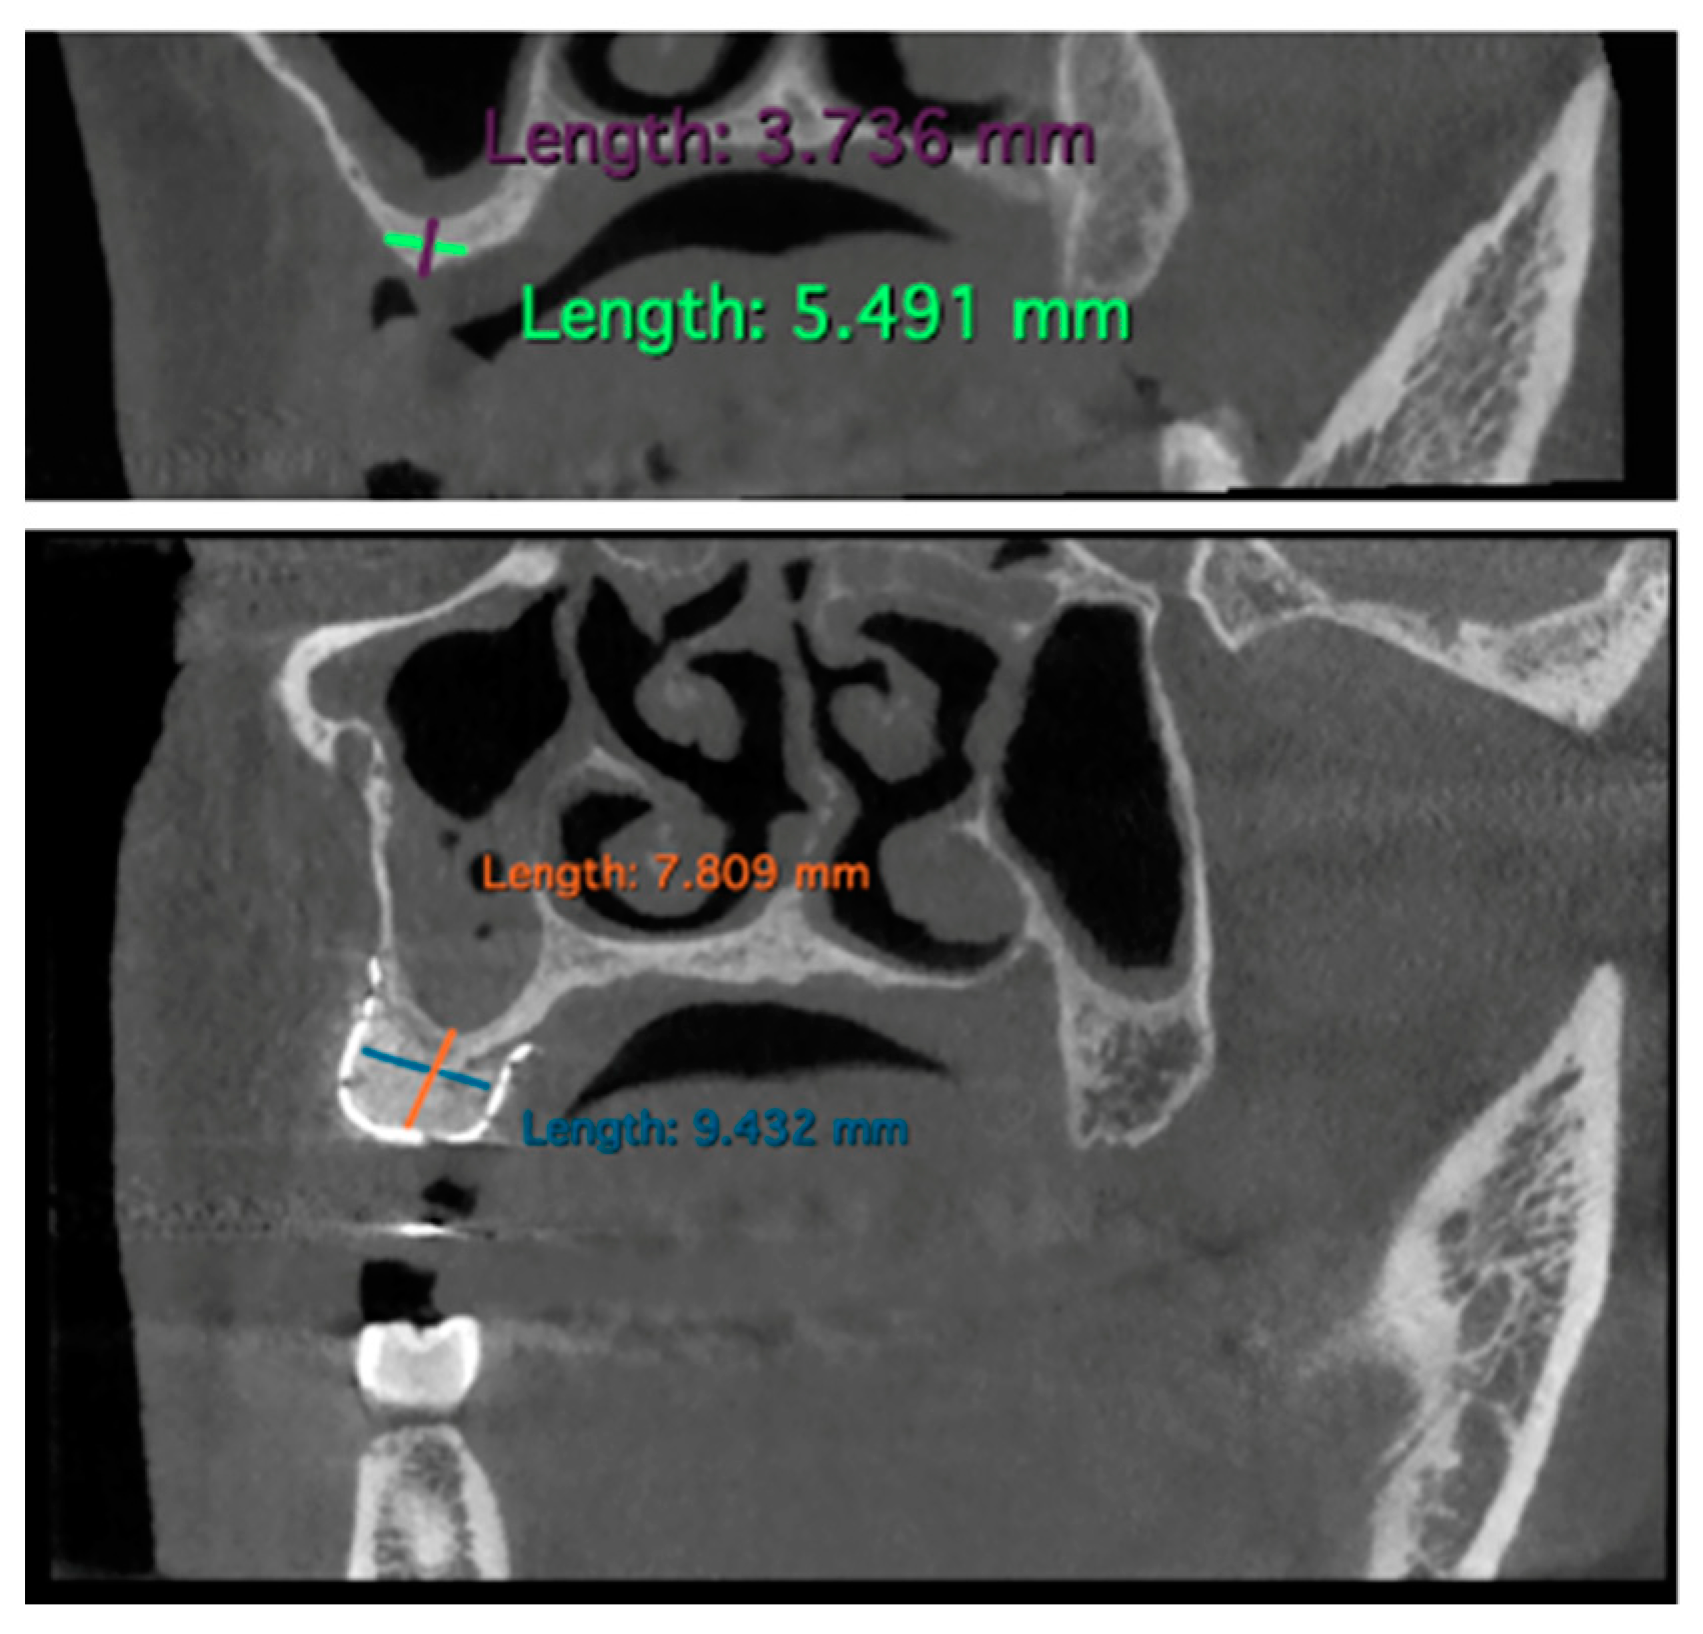

Bone gain measurements were conducted by comparing each patient’s preoperative and 6-month post-operative CBCT data.

Specifically, parasagittal images of the respective CBCTs were used as a reference for measuring bone defects. Mandibular bone defects were measured from the lower margin of the inferior alveolar nerve to the coronal portion of the bone defect. This approach aimed to prevent titanium mesh radiopacity from influencing post-operative result measurements, ensuring a complete identification of the inferior alveolar nerve.

The measurements were performed by using the software Horos Viewer™ (v.4.0.1) as shown in Figure 3.

The obtained results are summarized in Table 2. By comparing these data with those in Table 1, where measurements in terms of height, B-O extension (buccal–oral), and M-D extension (mesio-distal) are presented, it can be observed that in all cases, there was a sufficient bone increase, enabling the final placement of 24 total implants in 10 sites treated with the GBR technique.

Figure 3. Example of measurements performed on CBCT using the Horos Viewer™ software: pre-intervention and 6 months post-GBR (case n.10).